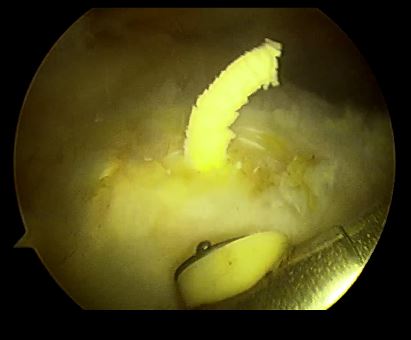

关节镜可以看见钙化灶有不同的表现,并在不同肌腱位置出现,手术中应该仔细寻找病变位置!

关节镜下钙化灶为石灰粉样、牙膏样

石膏样钙化灶

钙化灶为团块状